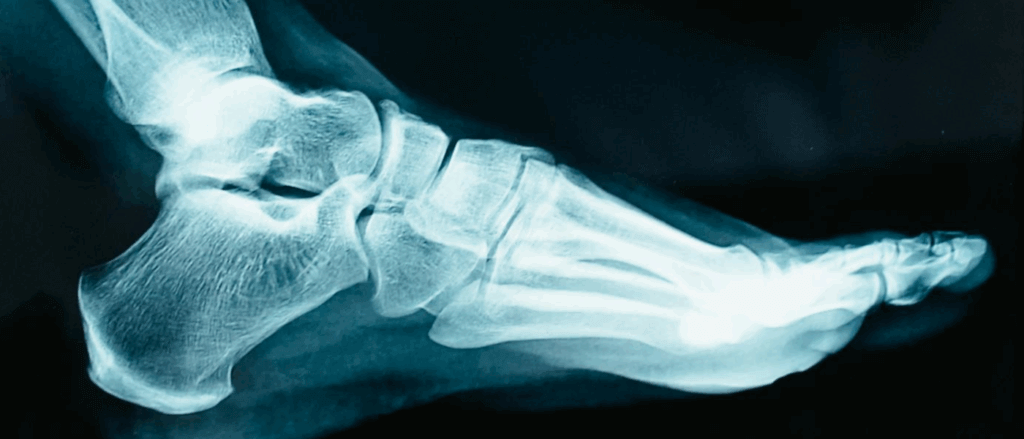

Work Accident